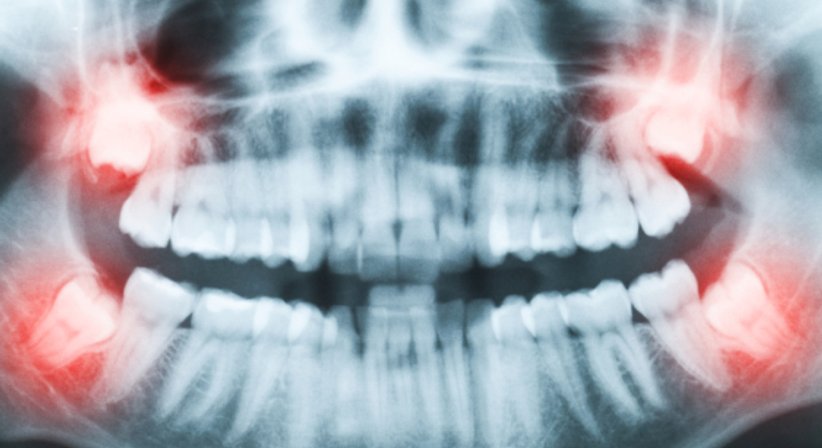

Weisheitszähne - Zysten

Von der Mitte aus gezählt ist der Weisheitszahn der achte Zahn im menschlichen Gebiss. Im Regelfall befindet sich in jedem Quadranten ein Weisheitszahn. Da sich im Laufe der Zeit das Gebiss des Menschen verkürzt hat, findet der Weisheitszahn bei vielen Menschen beim Durchbrechen nicht mehr ausreichend Platz. In weiterer Folge kann es zu Entzündungen, Abszessen, starken Schmerzen sowie zu einer behinderten Kaufunktion und Kiefergelenksbeschwerden kommen.

Bei einer Zyste handelt es sich um einen mit Flüssigkeit gefüllten Hohlraum. Zysten können in Knochen und in weichem Gewebe vorkommen, wobei der Kieferknochen besonders häufig betroffen ist. Es gibt verschiedene Arten von Zysten, im Bereich des Kiefers gehen die Zysten häufig von den Zahnwurzeln und Zahnkronen aus.

Mögliche Ursachen einer Zyste sind Entzündungen und Infektionen. Die Größe der Zyste ist abhängig von der Menge der Flüssigkeit. Patienten verspüren Schmerzen, sobald die Zyste beginnt Druck auf das umliegende Gewebe auszuüben.